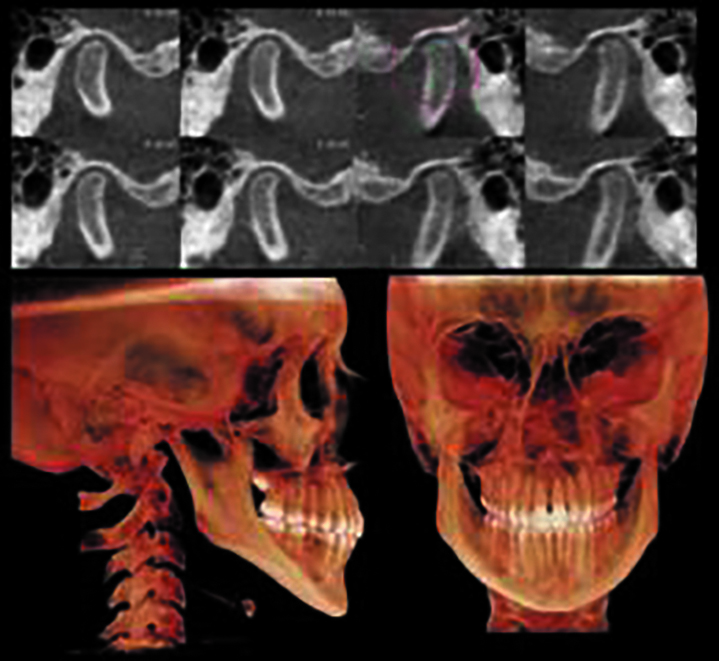

В ходе данного исследования авторы сочли целесообразным отдельно изучать высоту мыщелкового отростка во избежание некорретного измерения высоты ветвей (в случаях дегенеративных изменений мыщелкового отростка). Дегенеративное заболевание ВНЧС — невоспалительное заболевание ВНЧС (как и другого синовиального сустава), клинически проявляющееся интракапсулярной болью и проблемами с диском и характеризующееся деструкцией и восстановлением артикуляционного хряща и подлежащей субхондральной кости (рис. 1).

Рис. 1. Схема патогенеза дегенеративных заболеваний височнонижнечелюстного сустава (по Хатчеру).

Длину ветвей нижней челюсти и высоту мыщелкового отростка определяли по следующей методике. Для правой и левой сторон определялись четыре точки: Co (наиболее верхняя точка мыщелка), Cd (наиболее задняя точка мыщелка, вид сзади), Go (наиболее нижняя точка гониального угла нижней челюсти, латеральный вид), In (вырезка нижней челюсти) и два линейных измерения (Go-Cd и In-Co) проводились по касательной к заднему краю ветви нижней челюсти (рис. 2).

Рис. 2. Измерение длины ветви нижней челюсти и высоты мыщелкового отростка (Go-Cd и In-Co) по касательной к заднему краю ветви нижней челюсти.